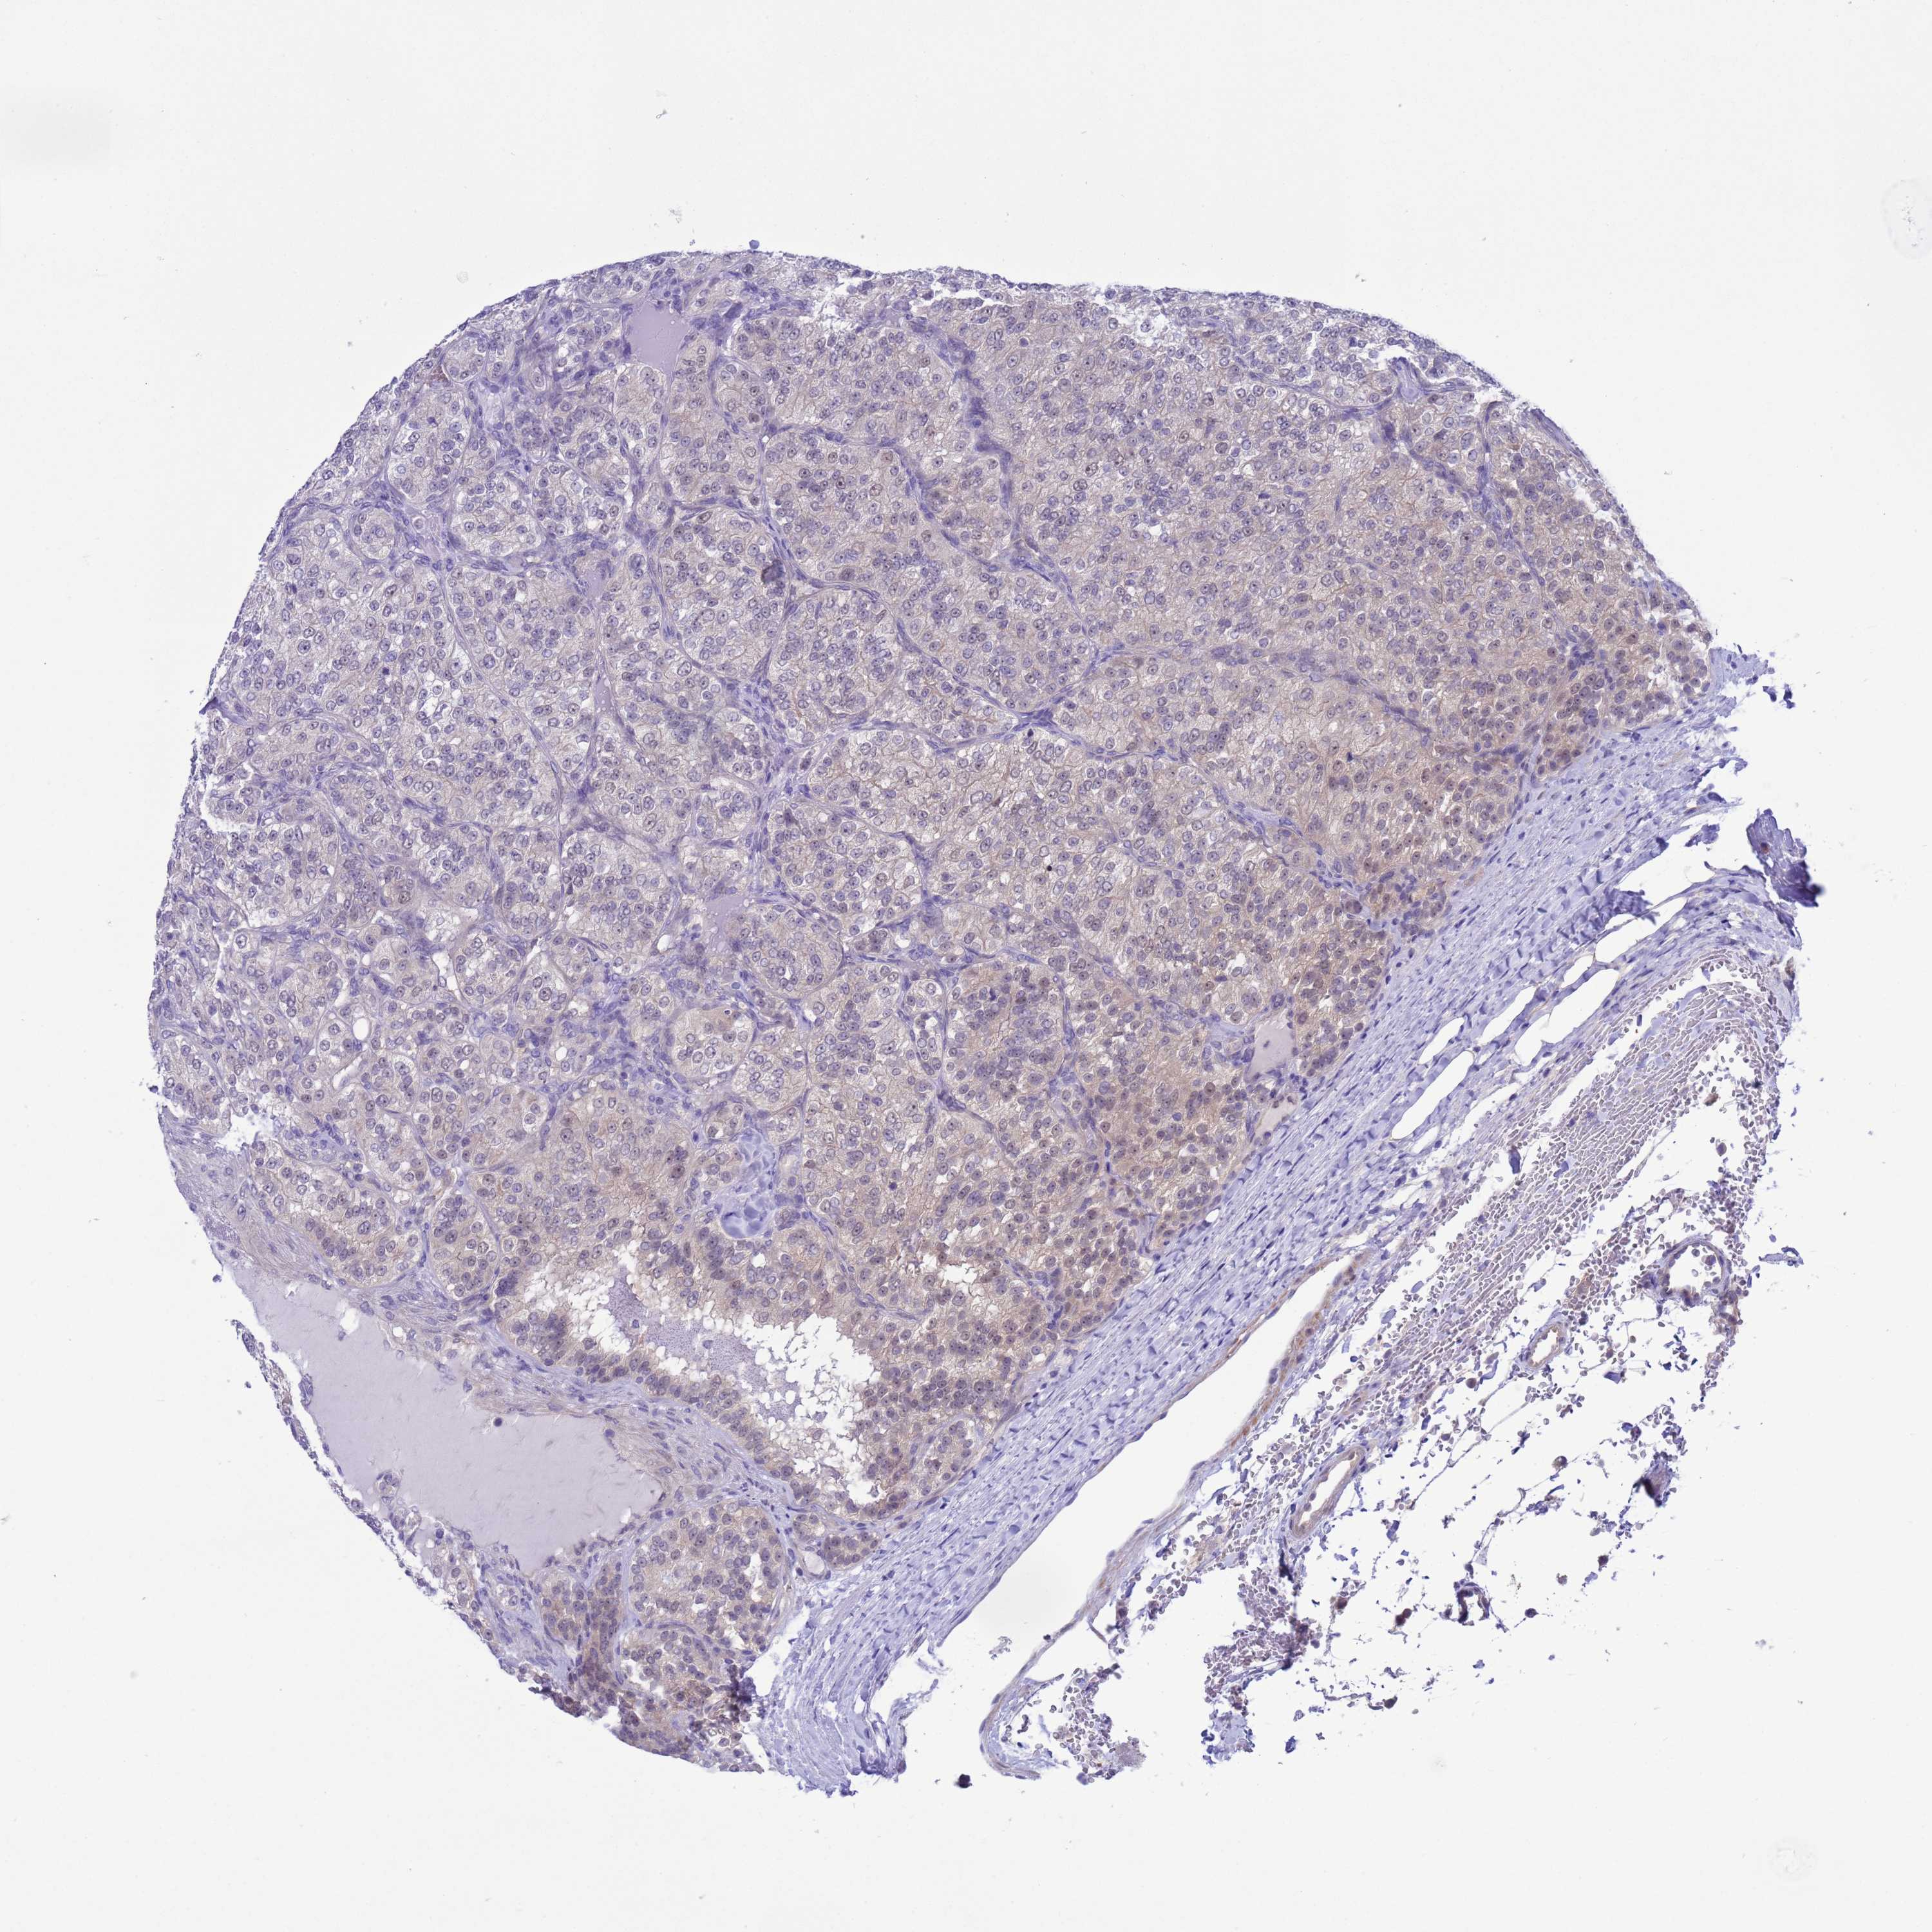

KIDNEY RENAL PAPILLARY CELL CARCINOMA (TCGA) - Interactive survival scatter ploti

The Survival Scatter plot shows the clinical status (i.e. dead or alive) for all individuals in the patient cohort, based on the same data that underlies the corresponding Kaplan-Meier plots. Patients that are alive at last time for follow-up are shown in blue and patients who have died during the study are shown in red.

The x-axis shows the expression levels (FPKM) of the investigated gene in the tumor tissue at the time of diagnosis. The y-axis shows the follow-up time after diagnosis (years). Both axes are complimented with kernel density curves demonstrating the data density over the axes. The top density plot shows the expression levels (FPKM) distribution among dead (red) and alive patients (blue). The right density plot shows the data density of the survived years of dead patients with high and low expression levels respectively, stratified using the cutoff indicated by the vertical dashed line through the Survival Scatter plot. This cutoff is automatically defined based on the FPKM cutoff that minimizes the p-score. The cutoff can be changed by dragging the vertical line or by entering a cutoff value in the square labeled "Current cut-off".

Under the Survival Scatter plot the p-score landscape (black curve; left axis) is shown together with dead median separation (red curve; right axis). Dead median separation is the difference in median mRNA expression between patients who have died with high and low expression, respectively. It is calculated as follows: median FPKM expression of dead patients with high expression - median FPKM expression of dead patients with low expression. This is intended to aid the user in visually exploring custom cutoffs and the associated p-scores and dead median separation.

Individual patient data is displayed and can be filtered by clicking on one or more of the category buttons on the top of the page. Categories describing expression level and patient information include: high, low, alive, dead, female, male and tumor stages. The scale of the x-axis can be toggled between linear and log-scale by clicking on the "x log" button. Mouse-over function shows TCGA ID, patient information and mRNA expression (FPKM) for each patient.

& Survival analysisi

Kaplan-Meier plots summarize results from analysis of correlation between mRNA expression level and patient survival. Patients were divided based on level of expression into one of the two groups "low" (under cut off) or "high" (over cut off). X-axis shows time for survival (years) and y-axis shows the probability of survival, where 1.0 corresponds to 100 percent.

ZNF461 is not prognostic in Kidney Renal Papillary Cell Carcinoma (TCGA)

Best expression cut offi

: 1.24